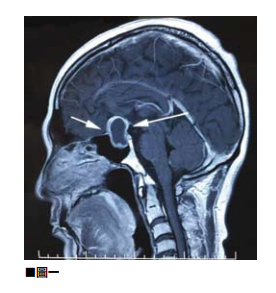

圖說01

所謂硬腦膜上出血是指,頭顱在受到撞擊後顱內血管受到創傷而流血,由於硬腦膜本身是保護腦部最外面的一層硬組織,倘若出血不是很嚴重則在傷後四至五天才會出現不尋常的劇烈頭痛。